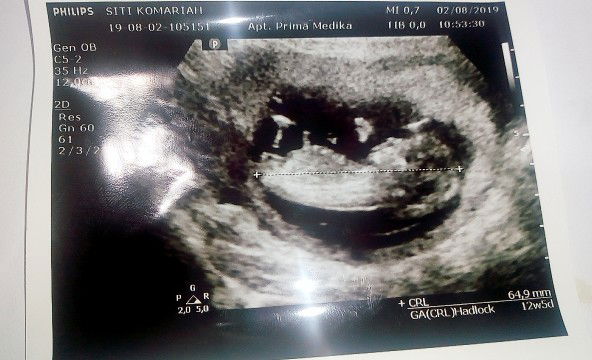

alhamdulilah bunda" saya tadi usg ddek nya alhamdulilah sehat dan aktip banget di dalem??? Tapy saya ada pertanya,an nih bunda" di sini di hasil usg nya ukuran ddek nya 64,9mm tapy saya liat di aplikasi ini berat nya 18,9g Apakah itu normal??